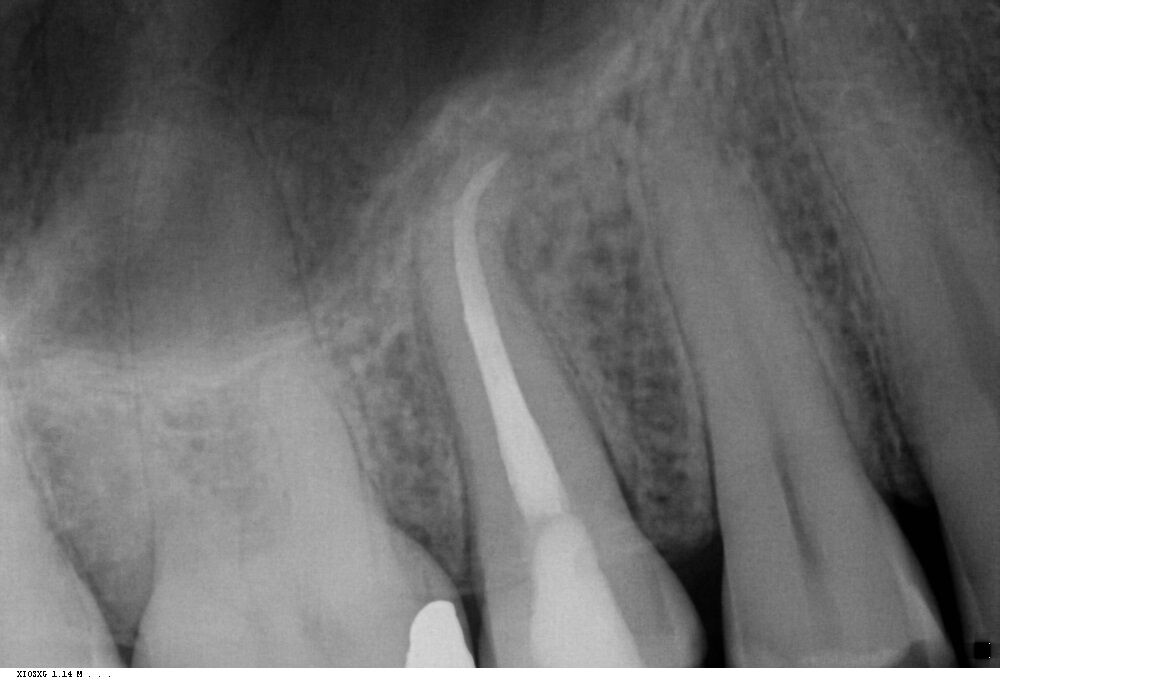

Fall 2: Entfernung eines Instrumentenfragmentes

Röntgenbild: Instrumentenfragment Ausgangssituation

Ausgangssituation